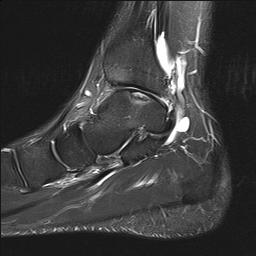

MRI

Stable lesion (Stage I) - cartilage intact, no synovial fluid under lesion

Unstable lesions (Stage II or III) - cartilage breach, synovial fluid under lesion

Displaced lesion with resultant osteochondral defect

Stable lesion with intact cartilage and no synovial fluid under lesion

Stage III completely detached but not displaced